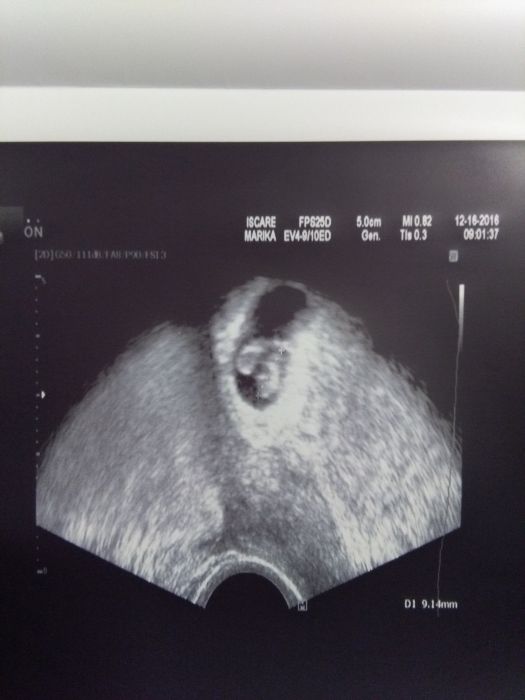

Holky vse je ok !!!!! Jsem 7+6, miminku bije srdicko :-) brecim jako zelva a furt koukam na fotky :-) doktorka me musela uzesovat :-) jestli jste slysely ranu jak hrom, tak to byl balvan, ktery ze me spadl :-)